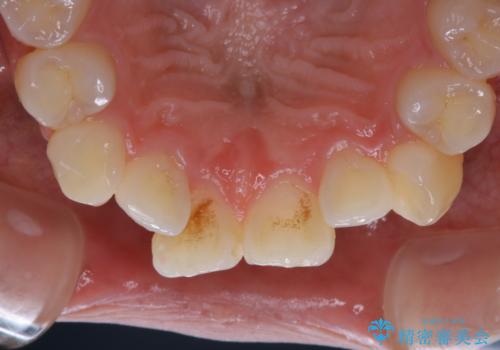

前歯のホワイトニング

- 当院にて矯正治療前の患者様です。検査にて前歯の根尖に病変を認めたため、矯正に先立ち前歯の治療を行いました。

変色の改善も希望されたため、歯のホワイトニング(ウォーキングブリーチ)にて対応しています。(根管治療はDr.林にて行っています。)

患者様には、矯正治療前に見た目の改善ができたと非常に満足して頂きました。